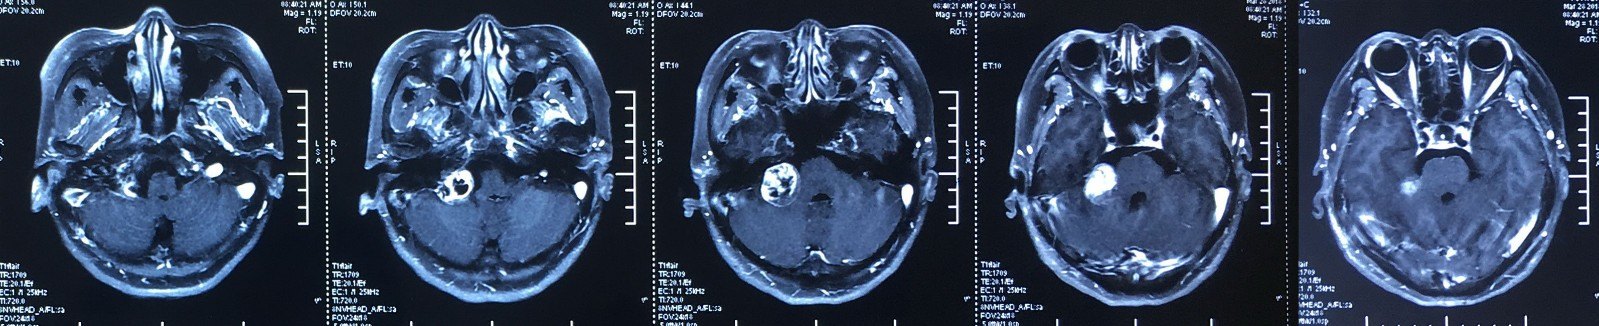

听神经瘤mri

图片尺寸1599x326